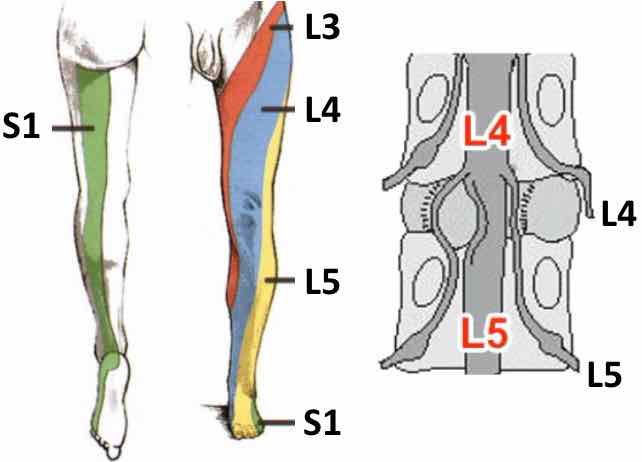

En L4-L5 : Etalement discal global avec composante foraminale, sans rétrécissement canalaire ou foraminal significatif ni argument en faveur d’un conflit discoradiculaire.

En L5-S1 : Etalement discal global avec composante foraminale, sans rétrécissement canalaire ou foraminal significatif ni argument en faveur d’un conflit discoradiculaire.